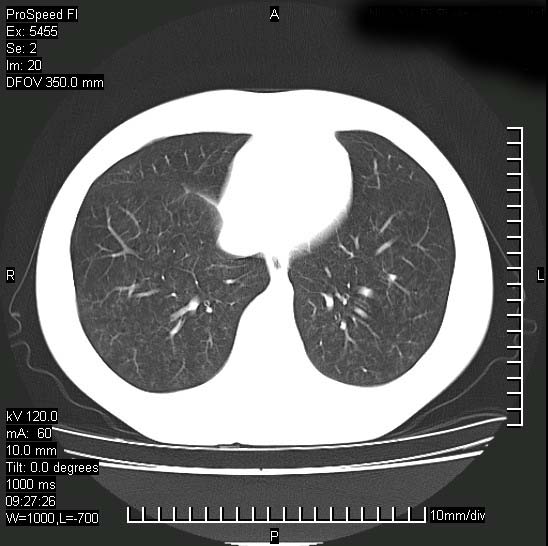

以下是引用zjzjr在2008-12-3 20:50:00的发言:[br]考虑泛细支气管肺炎,建议进一步检查除外肺出血性疾病如含铁血黄素沉着症、肺肾综合征等。

以下是引用zjzjr在2008-12-3 20:50:00的发言:[br]考虑泛细支气管肺炎,建议进一步检查除外肺出血性疾病如含铁血黄素沉着症、肺肾综合征等。

以下是引用光线在2008-12-3 20:19:00的发言:[br]双肺间质性改变。